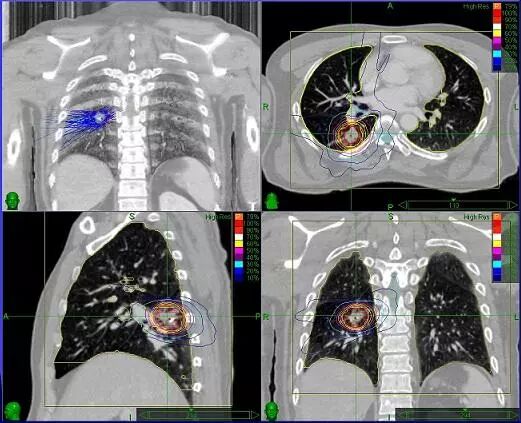

原发性肺癌接受CyberKnife治疗

根据反馈的信息,射波刀自动持续地以高精度定位每一次治疗光束,保证照射到运动中的肿瘤。直白地说,胸部或腹部的肿瘤(如肺癌、肝癌、胰腺癌等)都会随着呼吸运动而移动。而射波刀系统就可以实时追踪肿瘤的运动轨迹,保证每次射线都照射在肿瘤上。